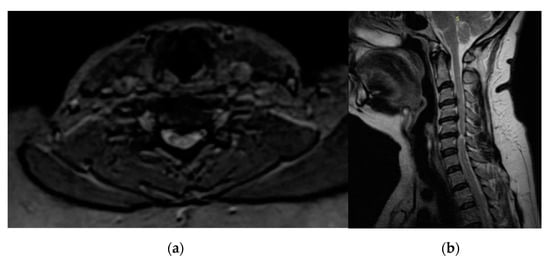

| Reporting results | Regarding DCM, the “snake-eye” appearance was regarded as a negative prognostic factor in 144 cases. In particular, in Mizuno’s study, the improvement ratio determined by JOA score was 32.2% in SEA (mean post-operative mJOA score of 12.9), 47.1% in non snake-eye appearance (NSEA), and 50% (p < 0.01) in control cases in which high signal intensity was absent. |